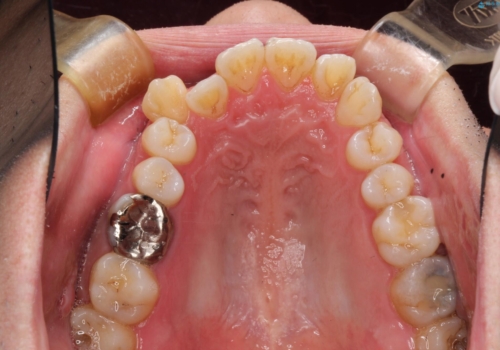

初診時の歯並びの状態としては、右上の犬歯がいわゆる八重歯の状態であり、強いガタガタが上下ともにある状態でした。

スペースの不足量が多く、抜歯を伴うワイヤー矯正にて治療を行いました。

若干の口元の突出感もあったため、抜歯によるスペースを利用し、がたつきの改善と前歯の後退をを行いました。